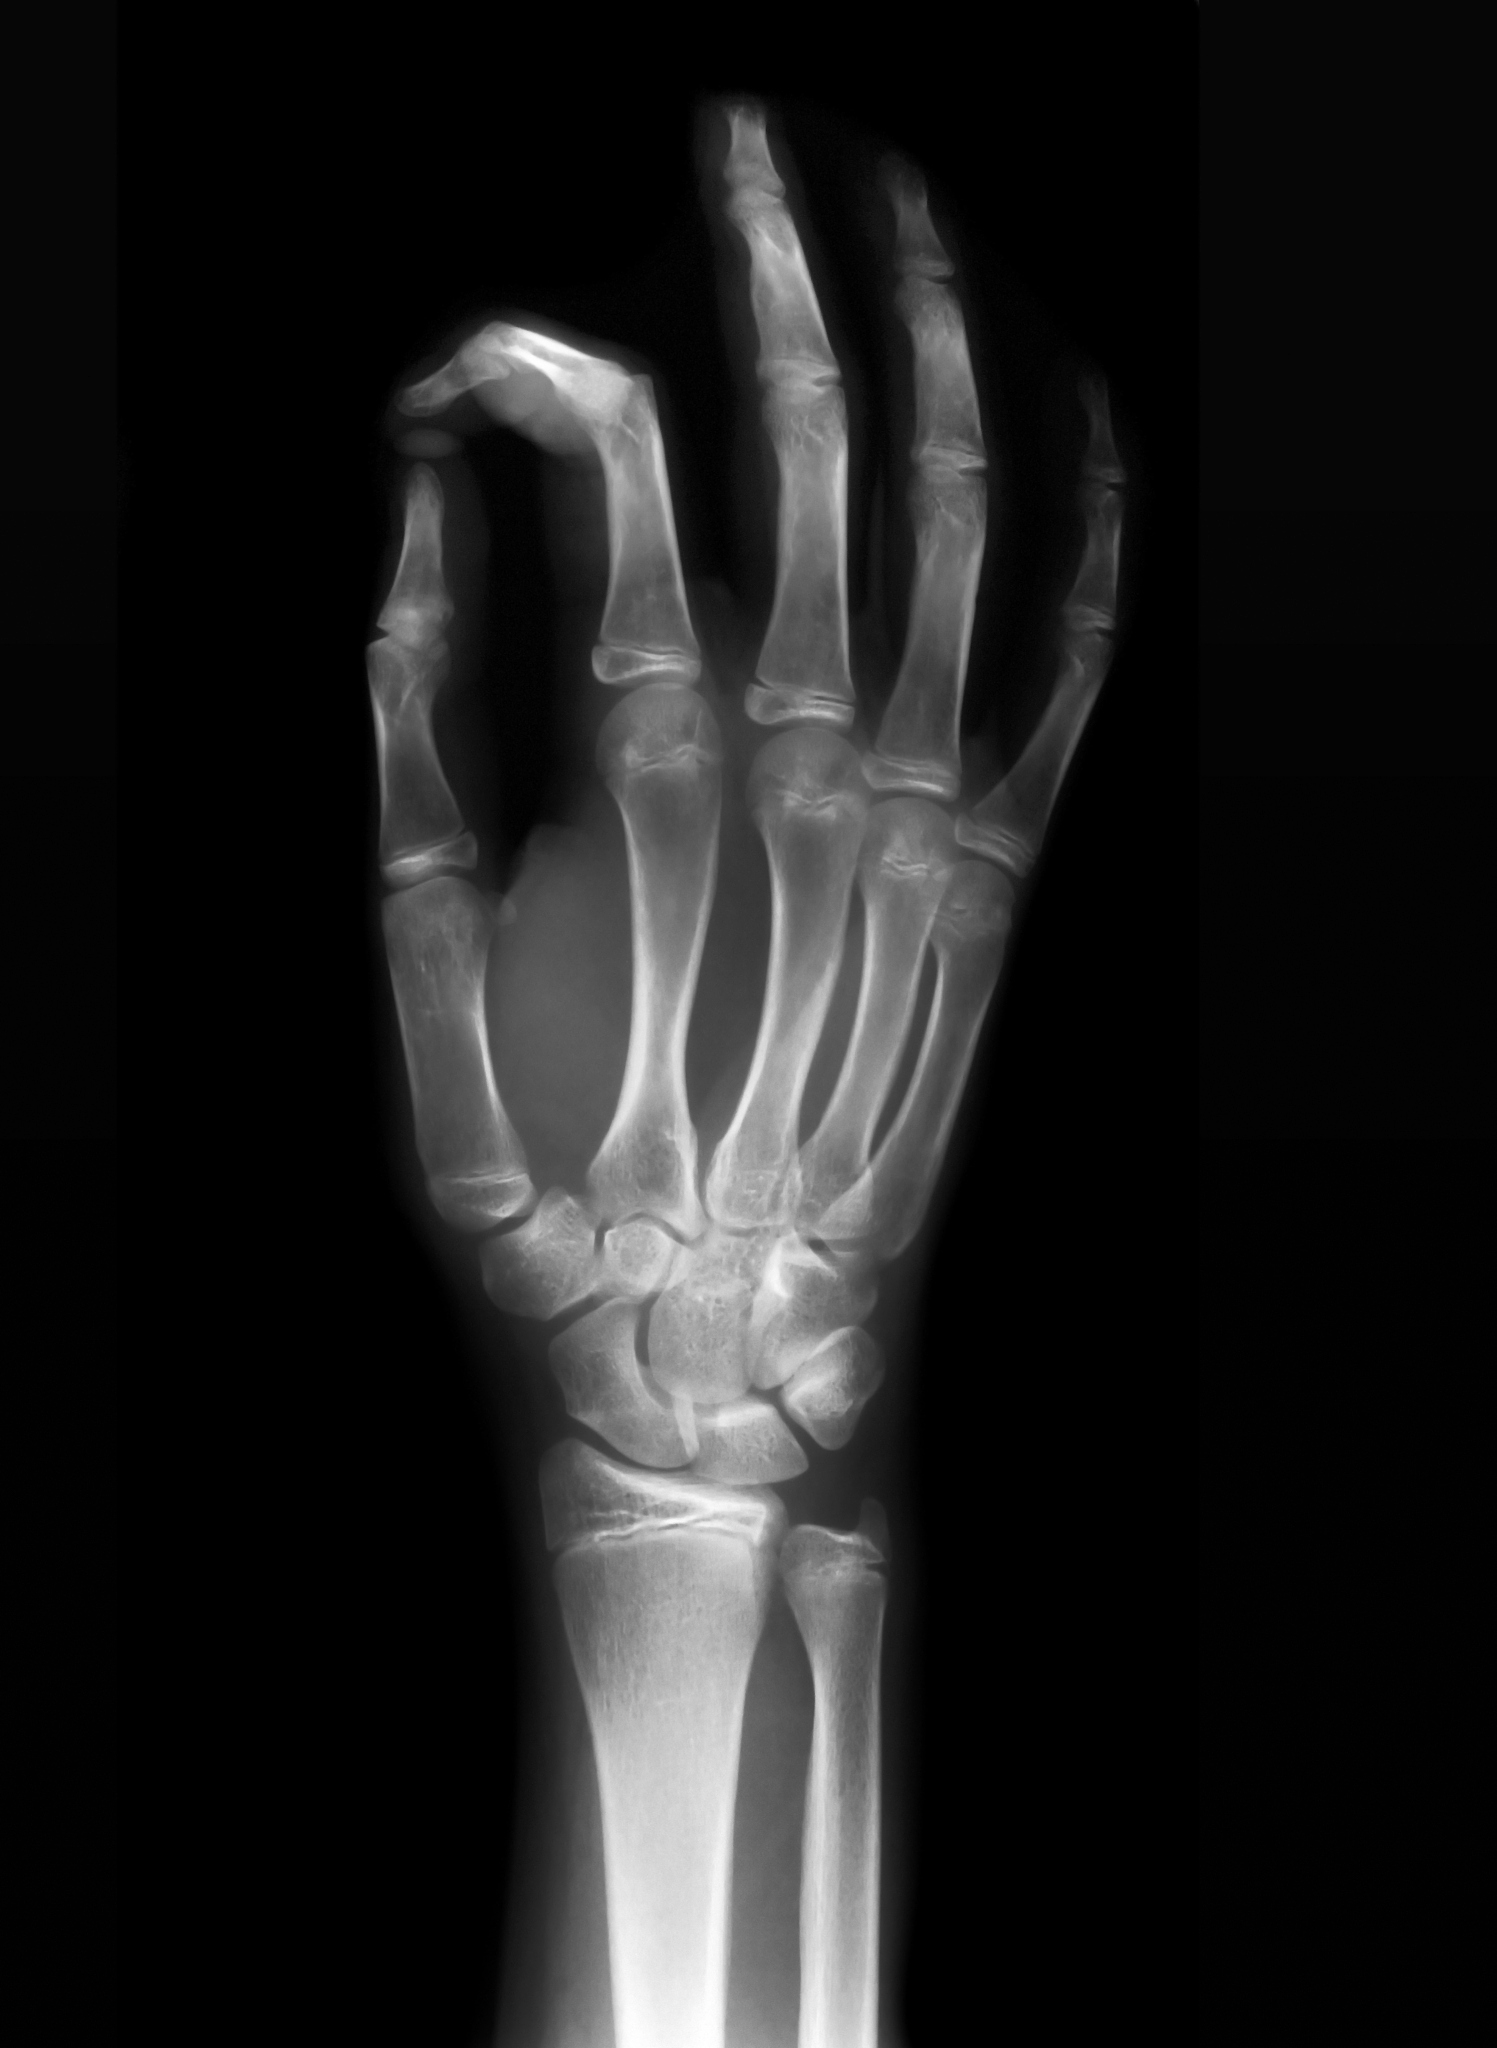

X线拍片法是通过对儿童的手腕、手掌、膝盖等部位进行X线拍片,然后根据骨骼发育情况来判断其骨龄。这种方法主要依赖医生的经验和专业知识,需要通过对多个部位的不同角度的拍片进行分析。

传统的骨龄预测方法虽然准确度较高,但需要专业人员进行操作,且存在较大的主观性和人为误差。同时,这种方法需要对儿童进行辐射检查,可能对儿童的健康造成一定的影响。因此,现在已经逐渐被计算机辅助骨龄预测方法所取代。